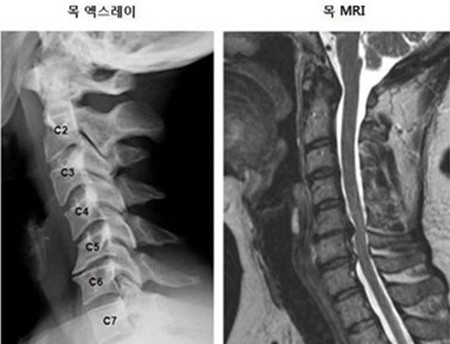

목 디스크는 목의 디스크(경추 디스크)에서 출현하는 질환으로, 경추 디스크 사이의 연골판이 터져 디스크 내부 물질이 경추 신경을 자극해 통증이나 저림증 등의 증상을 유발 해요. 목 디스크는 일상생활에서의 안 좋은 자세나 많은 운동, 부상 등이 이유가 되는 것이 될 수 있기도하고, 시간이 지날수록 발생 확률이 높아져요. 목 디스크의 증상으로는 목 부위의 통증, 팔의 저림, 근육 약화 등이 있으며, 증상이 난폭한 경우 수술 등의 치료가 필요할 수 있어요. 그리하나 대개의 경우 치료 없이도 시간이 지나면 증상이 호전되는 경우가 대부분입니다.

척수라는 중추 신경은 목뼈를 통과해 목 아래 감각과 운동 신경에 영향을 끼치기 때문에 목 디스크 증상들이 나타나면 신속하고 빠른 대처가 필요해요. 목디스크 치료형식으로 주로 초기 스탭에는 물리치료나 약물을 통해 대개의 환자들이 호전돼요. 그렇지 않다고 하면 신경 성형술과 차단술이라고 부르는 뼈주사 목디스크 치료방법을 이용하는데, 이 치료방법은 통증이 있는 신경 부위에 약물을 삽입하는 것입니다.

시술로써 눈에 띄게 질환을 현저히 치료하시는 것이 아니라 염증을 보완하고 통증을 낮추는 것이 포인트입니다. 이러한 방식으로 비 수술적인 치료를 3개월 이상 넘었음에도 불구하며 증상이 호전을 보이지 않으신다면 목디스크 치료방법 중 수술적 치료를 고심해야 하더라고요. 인공디스크를 투입하기 위함으로 절개를 통하기에 디스크를 제거하며 뼈를 하나로 유합 시켜서하는 것과, 내시경 수술로 빠져 나온 수핵 자체만을 제거시켜서하는 방법이 있다고하고요.

수술 방법에도 많은가 있다고 하는데 개괄적으로 설명을 하면 목을 절개해 망가진 디스크를 제거한 뒤 뼈를 하나로 유합하는 방법, 인공 디스크 투입술, 내시경을 활용해 바깥으로 빠져나온 수핵을 없애는 수술법 등이 있다고 합니다.